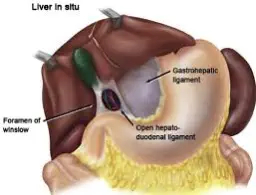

Wenn der Magen relativ häufig anschwillt, zum Beispiel durch Gärung der Nahrung im Magen, kann sich das so genannte Magen-Leber-Band (eine bindegewebige Verbindung zwischen Magen und Leber, das so genannte Ligamentum gastrohepaticum) langsam aber sicher dehnen, so dass der Magen mehr Bewegungsfreiheit hat.

Wissenschaftliche Studien zeigen, dass Hunde mit einem deutlich längeren Magen-Leber-Band und damit mit einer größeren Bewegungsfreiheit des Magens für eine Magendrehung prädisponiert sind.

Neben dem Magen-Leber-Band gibt es auch ein Band zwischen Leber und Dünndarm (Ligamentum hepatoduodenale), das unter anderem für die Fixierung des Magenausgangs (Pylorusfixierung) in der Bauchhöhle wichtig ist.

Dieses Band kann auch bei einer chronischen Magenschwellung gedehnt werden, wodurch sich das Risiko einer Magendrehung erhöht.

Wenn wir bei einem gesunden Hund den Magen-ausgang (Pylorus) manuell auf die gegenüber-liegende linke Seite der Bauchhöhle verschieben, wie es bei einer Magendrehung der Fall wäre, würde er, wenn wir den Magenausgang (Pylorus) wieder loslassen, theoretisch sofort wieder in seine normale physiologische Position auf der rechten Seite der Bauchhöhle zurückschießen. Im Gegensatz dazu würde bei einem Magen, bei dem zuvor eine Magendrehung stattgefunden hat, der Magenausgang in seiner abnormalen Position verbleiben und somit nicht in seine physiologische Position zurückschießen.